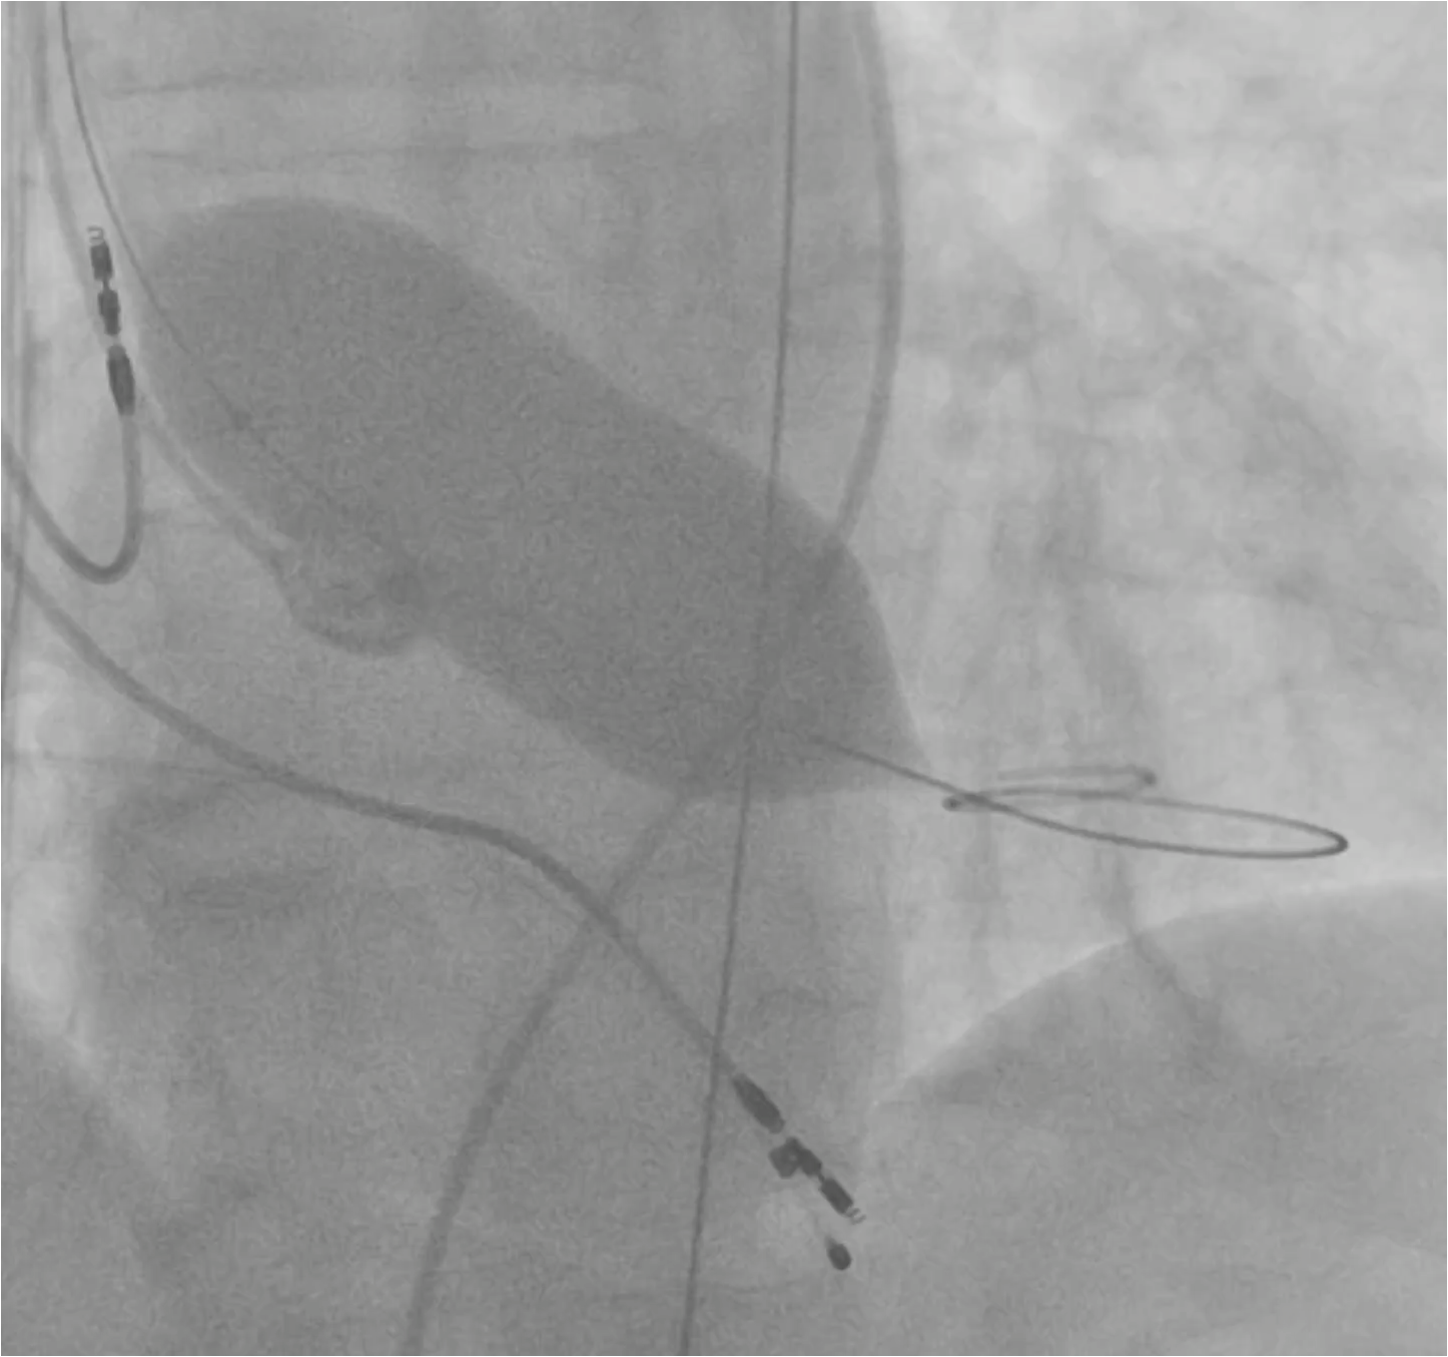

A super-rigid guidewire was inserted into the left ventricular cavity, and a valvulotomy was performed using a 23x40mm balloon catheter. After this, a successful implantation of a Portico 29mm aortic prosthesis was performed. During suturing of the access site, the patient developed persistent hypotension and bradycardia. A decision was made to perform catheterization of the left coronary artery trunk. During the angiogram, compression of the left coronary artery trunk by a hematoma in the projection of the fibrous ring was revealed. A decision was made to perform stenting of the left coronary artery trunk. The stent was successfully implanted in the left coronary artery trunk. Hemodynamics were restored. The patient was discharged on the 4th day after TAVI. A control MSCT was performed several months later.